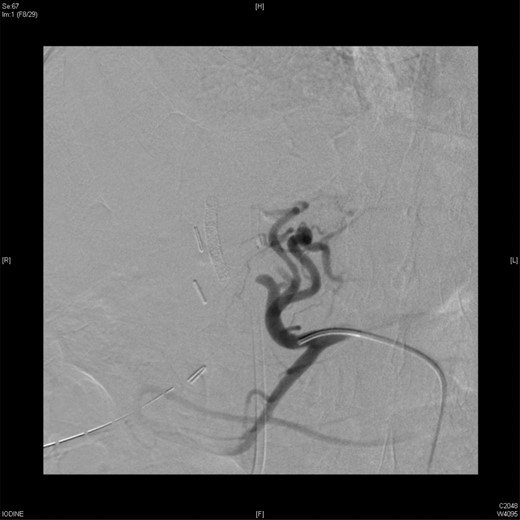

An angiographic scan showed stent in the replaced right hepatic artery.